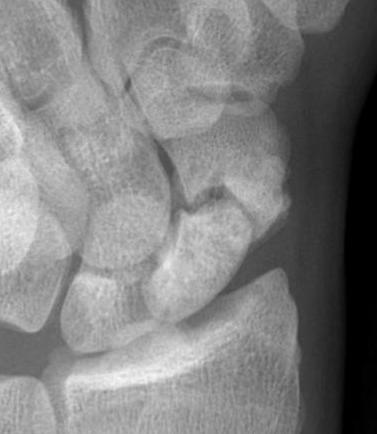

Xray

Increased sclerosis proximal pole consistent with AVN